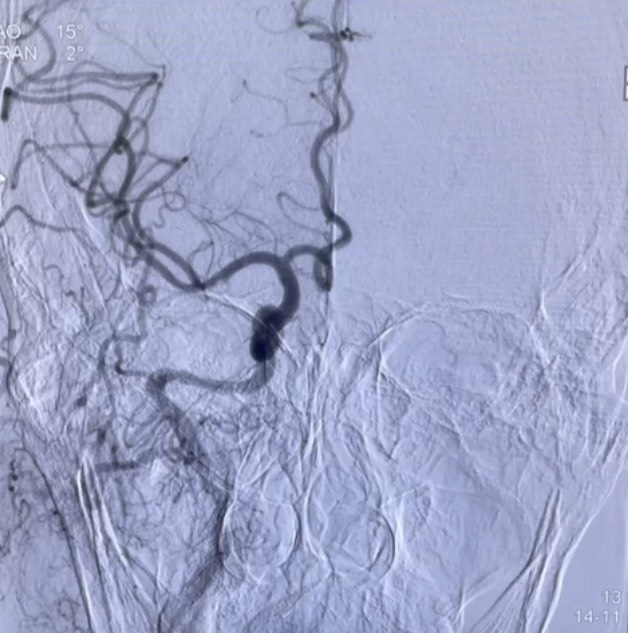

Điển hình là trường hợp bệnh nhân nữ L.T.N 69 tuổi, tiền sử khỏe mạnh, vào viện khoa Cấp cứu ngày 11/4/2025 vì lý do ý thức chậm, nói khó, méo miệng, liệt vận động hoàn toàn nửa người trái giờ thứ 3. Ngay sau khi tiếp nhận thông tin, bác sĩ trực và kíp can thiệp khoa Đột quỵ đã có mặt tại khoa Cấp cứu tiến hành thăm khám đánh giá bệnh nhân, kết hợp hình ảnh chụp CLVT sọ não và điện tim đồ bệnh nhân được chẩn đoán: Nhồi máu não cấp giờ thứ 4 do tắc động mạch não giữa bên phải/ Rung nhĩ. Xác định đây là trường hợp huyết khối tắc mạch lớn cần phải phối hợp các phương pháp điều trị, bác sĩ trực đã giải thích gia đình và tiến hành sử dụng thuốc tiêu sợi huyết đường tĩnh mạch đồng thời đẩy thẳng bệnh nhân lên phòng can thiệp mạch cấp cứu. Hình ảnh chụp mạch não số hóa xóa nền DSA cho thấy bệnh nhân bị tắc hoàn toàn động mạch não giữa bên phải. Kíp can thiệp đã triển khai phương pháp tái thông mạch não bằng dụng cụ cơ học. Kết quả, sau 02 lần hút đã tái thông hoàn toàn động mạch não giữa bên phải đạt mức TICI 3. Hiện tại ngày thứ 10 sau can thiệp, tình trạng bệnh nhân ổn định: Ý thức tỉnh G15đ, nói rõ, liệt nhẹ VII TW bên trái, liệt nửa người trái cải thiện tốt.

Hình ảnh trước và sau can thiệp tái thông mạch não bằng dụng cụ cơ học